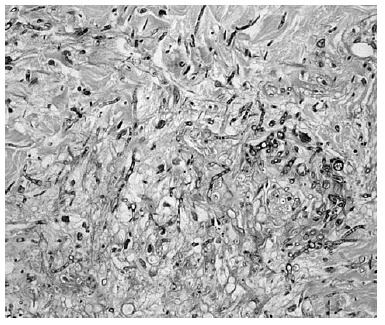

La biopsia de piel mostró discreta espongiosis y exocitosis linfocitaria en la epidermis, observándose en dermis papilar y reticular una intensa infiltración por elementos fúngicos en forma de hifas tabicadas y no tabicadas, en ocasiones bifurcadas, y por estructuras de tipo levaduriforme (fig. 2). Estas hifas tenían afinidad por las paredes vasculares a las que invadían (fig. 3). La respuesta inflamatoria acompañante es prácticamente nula. En el cultivo de la biopsia cutánea se identificó un hongo del género Fusarium, siendo los hemocultivos, cultivos del catéter y de esputo negativos.

Fig. 3.--Detalle de los hongos invadiendo la pared un vaso (PAS)